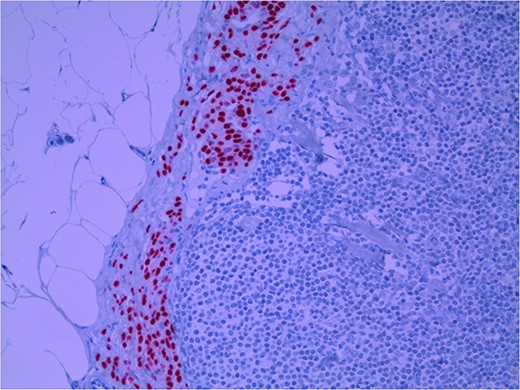

Lymph node specimens were sent for haematoxylin and eosin (H&E) staining (Fig. 3) and IHC analysis. The sections showed mild reactive changes and benign intracapsular nevoid rests. IHC analysis showed that these cells were negative for HMB-45 (Fig. 4) and were positive for both Sox10 and p16 (Figs 5 and 6). Consensus at the Multidisciplinary Team Meeting was that the appearance was in keeping with benign naevoid rests as opposed to melanoma deposits, given the location of the cells, morphology and immunohistochemistry. Surveillance was recommended.

Lymph node with IHC using Sox 10 stain, staining melanocytic cells (benign or malignant) in subcapsular region; × 200 magnification.

Several IHC stains are in use in the pathological interpretation of primary lesions and SLN biopsies. The antibody HMB-45 reacts with most melanomas. In a primary lesion, HMB-45 is immunoreactive with intraepidermal and superficial dermal components of benign nevi [14]. In a lymph node, however, benign nevoid cells are negative for HMB-45 and appear bland. A loss of HMB-45 expression has been reported in 20% of melanocytic metastasis, illustrating the need for further diagnostic testing [14]. Sox10 is a nuclear transcription factor that stains benign and malignant melanocytic cells. It indicates the extent of melanocytic spread but does not differentiate between benign nevi and metastatic melanoma [15]. Immunostaining for the tumour suppressor gene p16 differentiates between benign naevi and melanocytic metastases in the SLN. One study demonstrated positive nuclear and cytoplasmic p16 staining in all nevi (dermal and lymph node) and the absence of nuclear p16 staining in all but one melanoma metastasis [14]. No single stain is completely sensitive for melanocytic metastases, and a confident diagnosis relies upon cell location, morphology and multiple IHC techniques. SLN biopsy in the current patient demonstrated intracapsular melanocytic cells which stained negative for HMB-45, and positive for Sox10 and p16, in keeping with benign nevoid rests as opposed to metastatic melanoma.